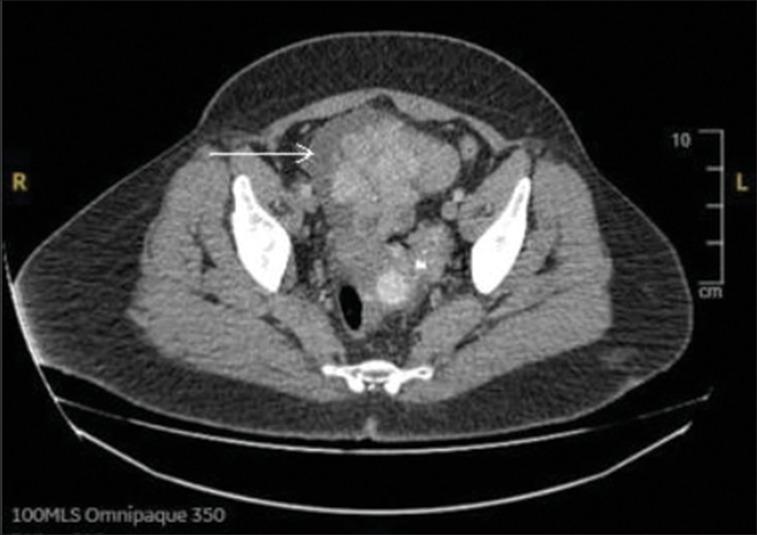

原发性卵巢类癌肿瘤是卵巢恶性肿瘤中极为罕见的一个亚型(占病例不到0.1%),通常表现为腹痛和腹胀。没有典型类癌综合征特征的类癌性心脏病(CHD)的发生极为罕见。我们报告一名54岁女性,数月来出现呼吸困难和水肿,缺乏典型的类癌综合征体征。初始评估诊断为心力衰竭,NT-Pro BNP升高、超声心动图显示右心室扩张以及肺/三尖瓣反流(左心室功能正常)均支持这一诊断。右心导管检查显示肺/右心室压力正常。随后的检查(胸部、腹部、盆腔计算机断层扫描以及5-羟色胺乙酸水平检测)强烈提示类癌病,奥曲肽扫描显示分泌奥曲肽的卵巢类癌肿瘤,从而确诊。手术干预包括三尖瓣和肺动脉瓣修复、全腹子宫切除术以及双侧输卵管卵巢切除术。原发性卵巢类癌肿瘤虽然罕见,但可能导致如CHD等意想不到的并发症。对于此类病例,及时诊断和干预对于优化患者预后至关重要。